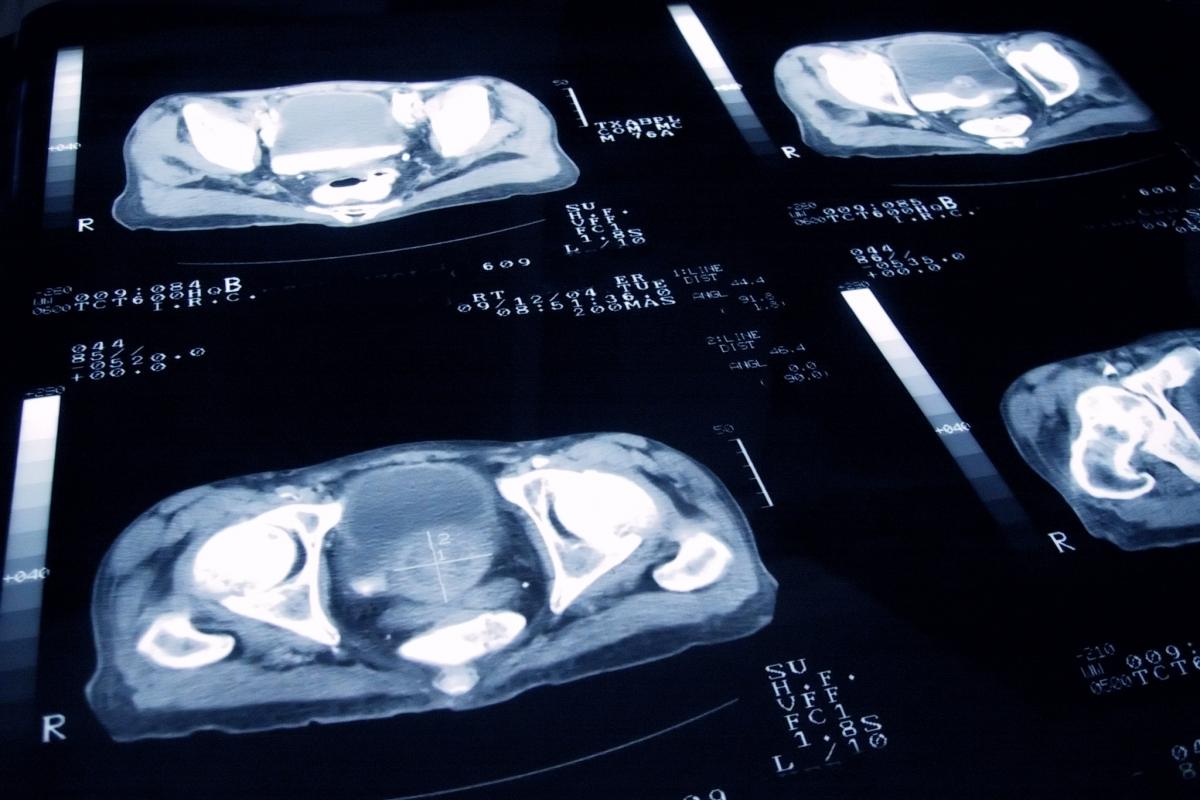

El cáncer de próstata es el más común entre los hombres en España, por eso en los últimos años se han dedicado recursos y tiempo para intentar encontrar métodos de diagnóstico más efectivos y tempranos, que permitan aplicar tratamientos más adecuados para eliminar la enfermedad.

Según los expertos, el problema de los malos diagnósticos de cáncer de próstata es que suelen producirse cuando el cáncer está bastante avanzado y es más difícil de tratar, mientras que si la detección fuera temprana los tratamientos serían más efectivos.